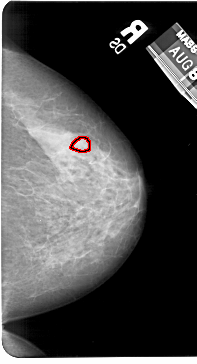

A_1602_1.LEFT_MLO

FILE: A_1602_1.RIGHT_MLO.OVERLAY

TOTAL_ABNORMALITIES 1

ABNORMALITY 1

LESION_TYPE MASS SHAPE LOBULATED MARGINS OBSCURED

ASSESSMENT 4

SUBTLETY 2

PATHOLOGY BENIGN

TOTAL_OUTLINES 1

BOUNDARY